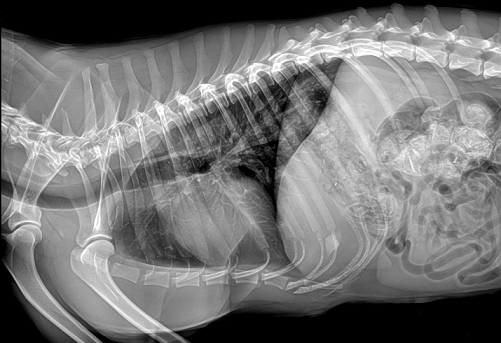

普爱医疗宠物DR采用非晶硅DR平板探测器,确保优异的图像质量,提供可靠的临床诊断。短时间快速成像,工作效率更高,无需洗片,电脑直接成像。

普爱医疗品牌的宠物DR影像成像

高品质组合式X射线发生器,大大减少射线辐射,对环境保护及操作人员更安全。同时,普爱医疗的宠物DR可用于宠物医院放射室、宠物诊所等宠物医疗机构,满足不同体型宠物的全身各部位的wsgtexr摄影工作需求。想了解产品具体信息,欢迎留言或致电400-6656-888